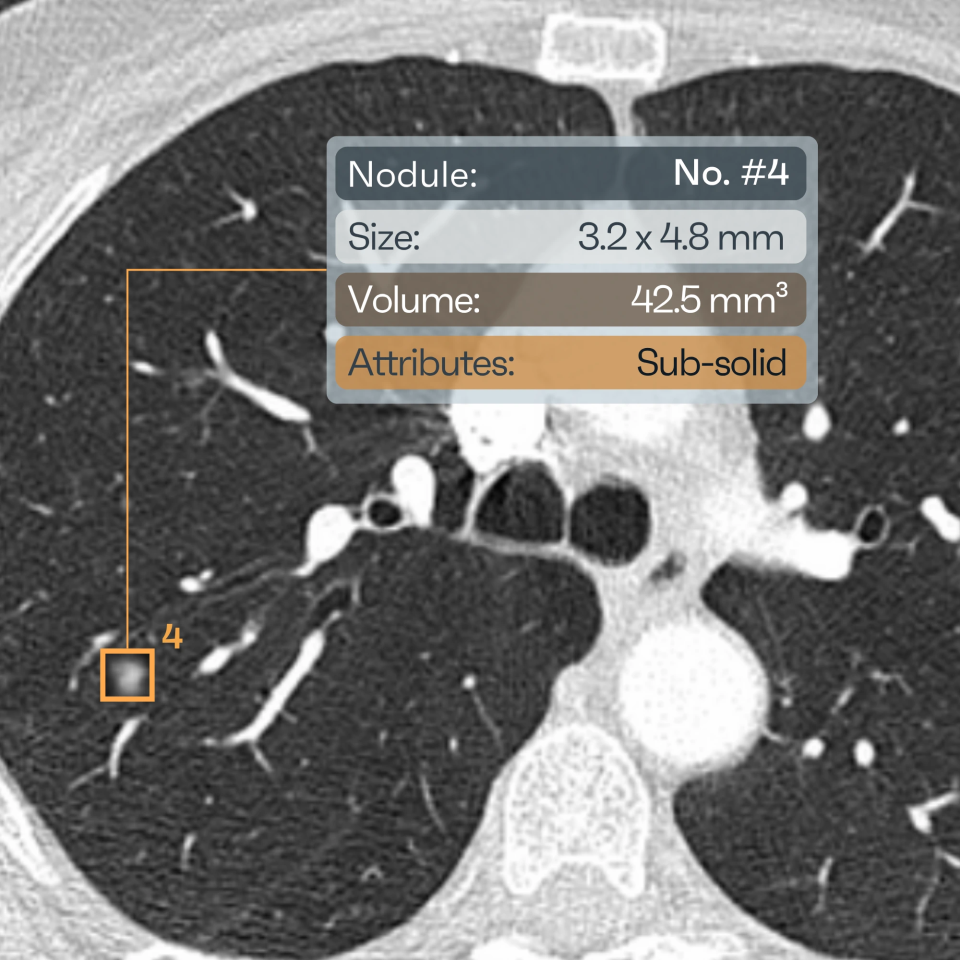

NODULE INFORMATION